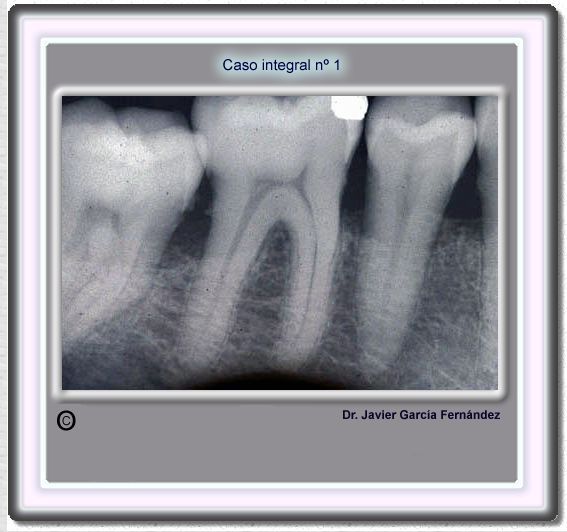

image 22